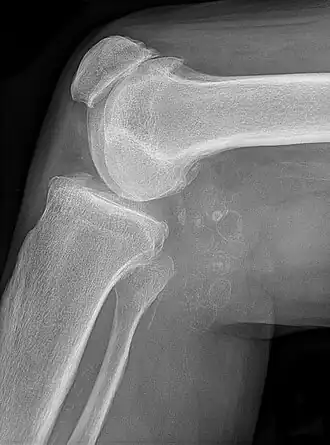

Description de cette image, également commentée ci-après

Chondromatose synoviale avec chondromes multiples dans le kyste de Baker, liés à une gonarthrose.